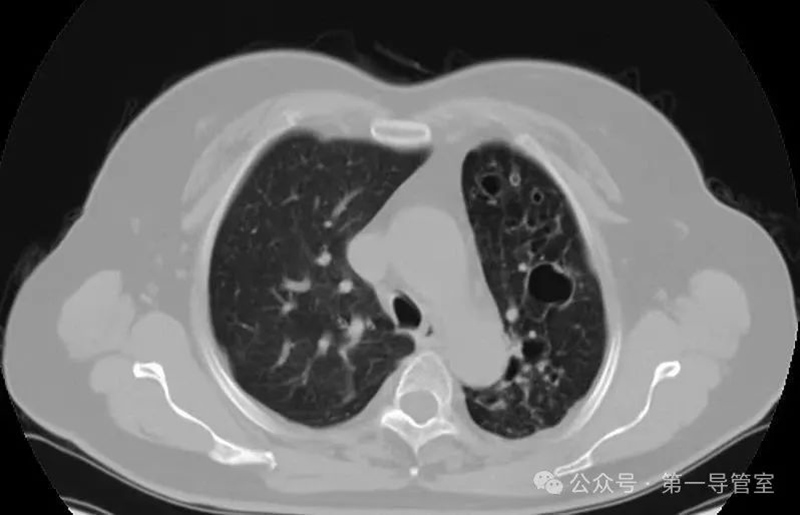

胸部CT顯示:左肺多發(fā)囊狀擴張支氣管影,考慮為支氣管擴張合并感染。確診后,經(jīng)驗豐富的崔曉杰主任迅速安排張女士入院接受治療,制定了周全的綜合治療方案:吸氧、止血、止咳平喘及抗感染等綜合治療。盡管如此,在治療過程中,張女士依然出現(xiàn)了頻繁的咳血癥狀,血量最多時達90ml/天,這使得她的病情變得極為嚴(yán)峻,令人擔(dān)憂。